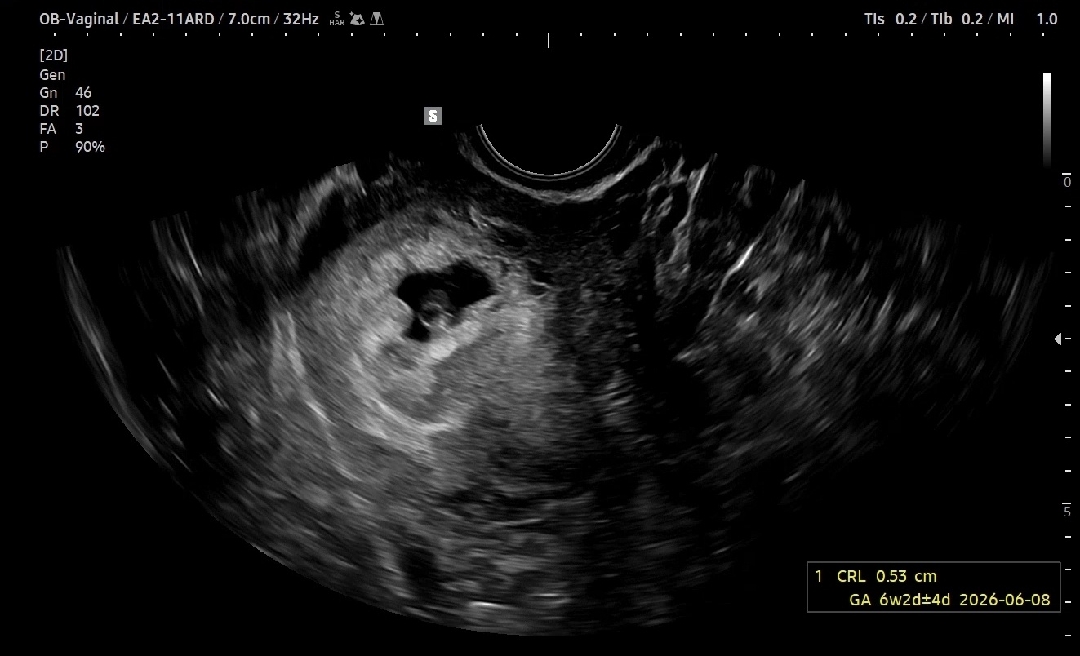

6주 2일차 심장소리

올해초 7주차 계류유산 후 6개월만에 다시 찾아와준 아기 임신을 깨닫기 5일전에 39도 고열로 응급실에 갔었는데 그때 상주해있던 간호사가 피검사 후 임신확률이 없다고 해서 마음 편하게 센 약물치료로 열 내리고 집에 왔는데.. 5일뒤에 생리예정일에 생리를 안해서(27-29일주기는 무조건 지키는 편) 테스트기를 해보니 두줄. 아기 잘못될까봐 전전긍긍했는데 다행히 4주4일차에는 아기집은 안보이고 피검사 753으로 정상임신 소견들었어요. 5주4일차 아기집+막 생기려고 하는 난황보고 오늘 6주4일차때 >6주2일차로 조정되고 우렁찬 심장소리(125)까지 듣고왔네요 년초에는 주수에 맞게 자라지않고 심장이 뛰다가 멈춰서 지켜주지 못 했는데 이런 악상황속에서 잘 커주고 있어서 병원에서 펑펑 울었어요 다음주에도 꼭 잘 자라주길 기도하고 있습니다 저도 여기 계신분들처럼 꼭 건강한 아이 제 품에 안고싶네요..ㅠㅠ